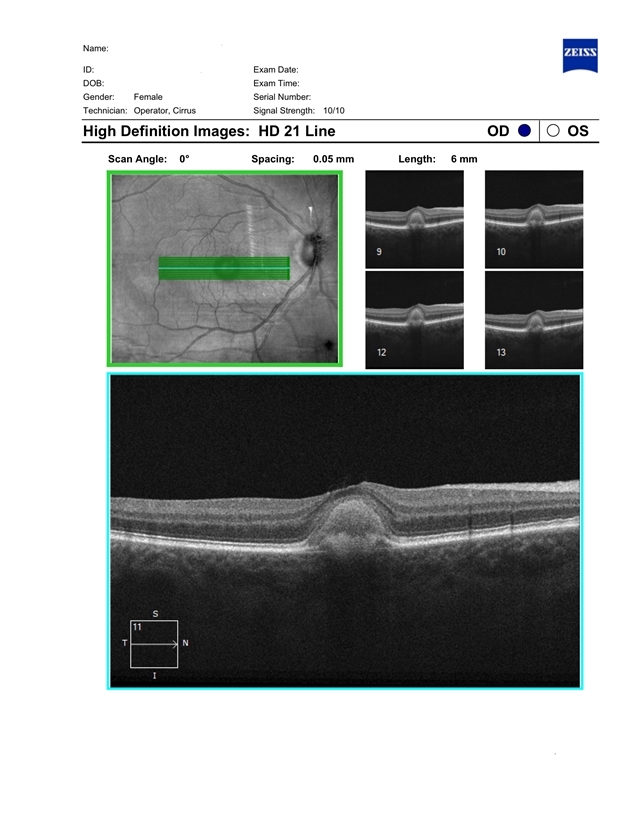

- vitelliform macular dystrophy, adult vitelliform dystrophy, vitelliform lesion

- Optical coherence tomography system

- Patient born in 1946. Concerns about decreased vision in right eye, distortions when reading. The ocular fundus of both eyes shows round yellowish deposits (vitelliform material deposits) in the fovea. Autofluorescence photography reveals hyperautofluorescence. OCT demonstrates the presence of vitelliform material under the sensitive retina and over the retinal pigment epithelium.